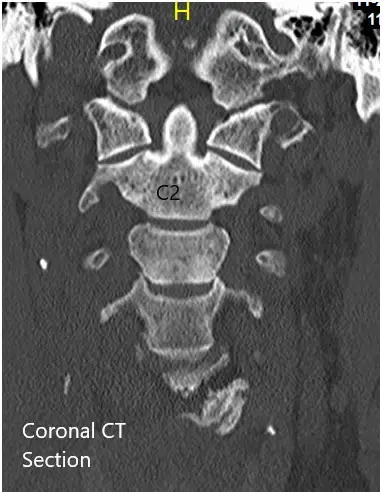

La TC de la columna cervical mostró protrusiones discales posteriores de varios niveles con estenosis foraminal neural bilateral de la columna cervical media a baja. Los cambios degenerativos hipertróficos escleróticos se asociaron con las facetas cervicales medias a bajas.

TAC coronal y axial preoperatorio.